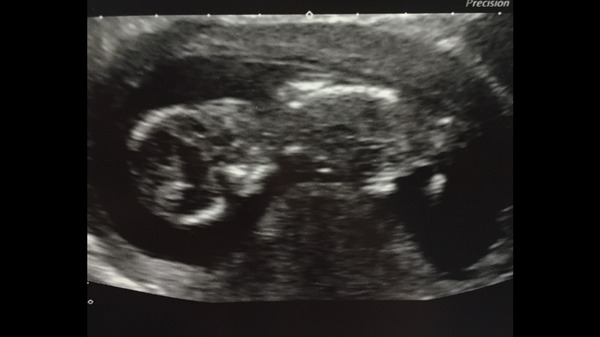

Scan went well! Baby was asleep and curled up so after a bit of prodding and poking it got moving!

NT measurement was 1.5 - no idea what that means, had my blood test they said no news is good news, bad news would come by phone in 3-4 days.

They had a look but couldn't tell the sex of the baby as it wasn't facing us! Baby was facing my back / upside down most of the time.

I am so happy, felt sad OH wasn't there, but we got a picture so that was good.

My dates have been changed again! Now gone from the 18th to the 25th and back to the 19th now, so 14 weeks on Sunday.

Number3cometome · 15/01/2015 18:53

Baby x

number3 what a super scan pic Grin

awh, lovely pic :)

Lovely pic number.

number love the picture.

What a lovely picture, Number!